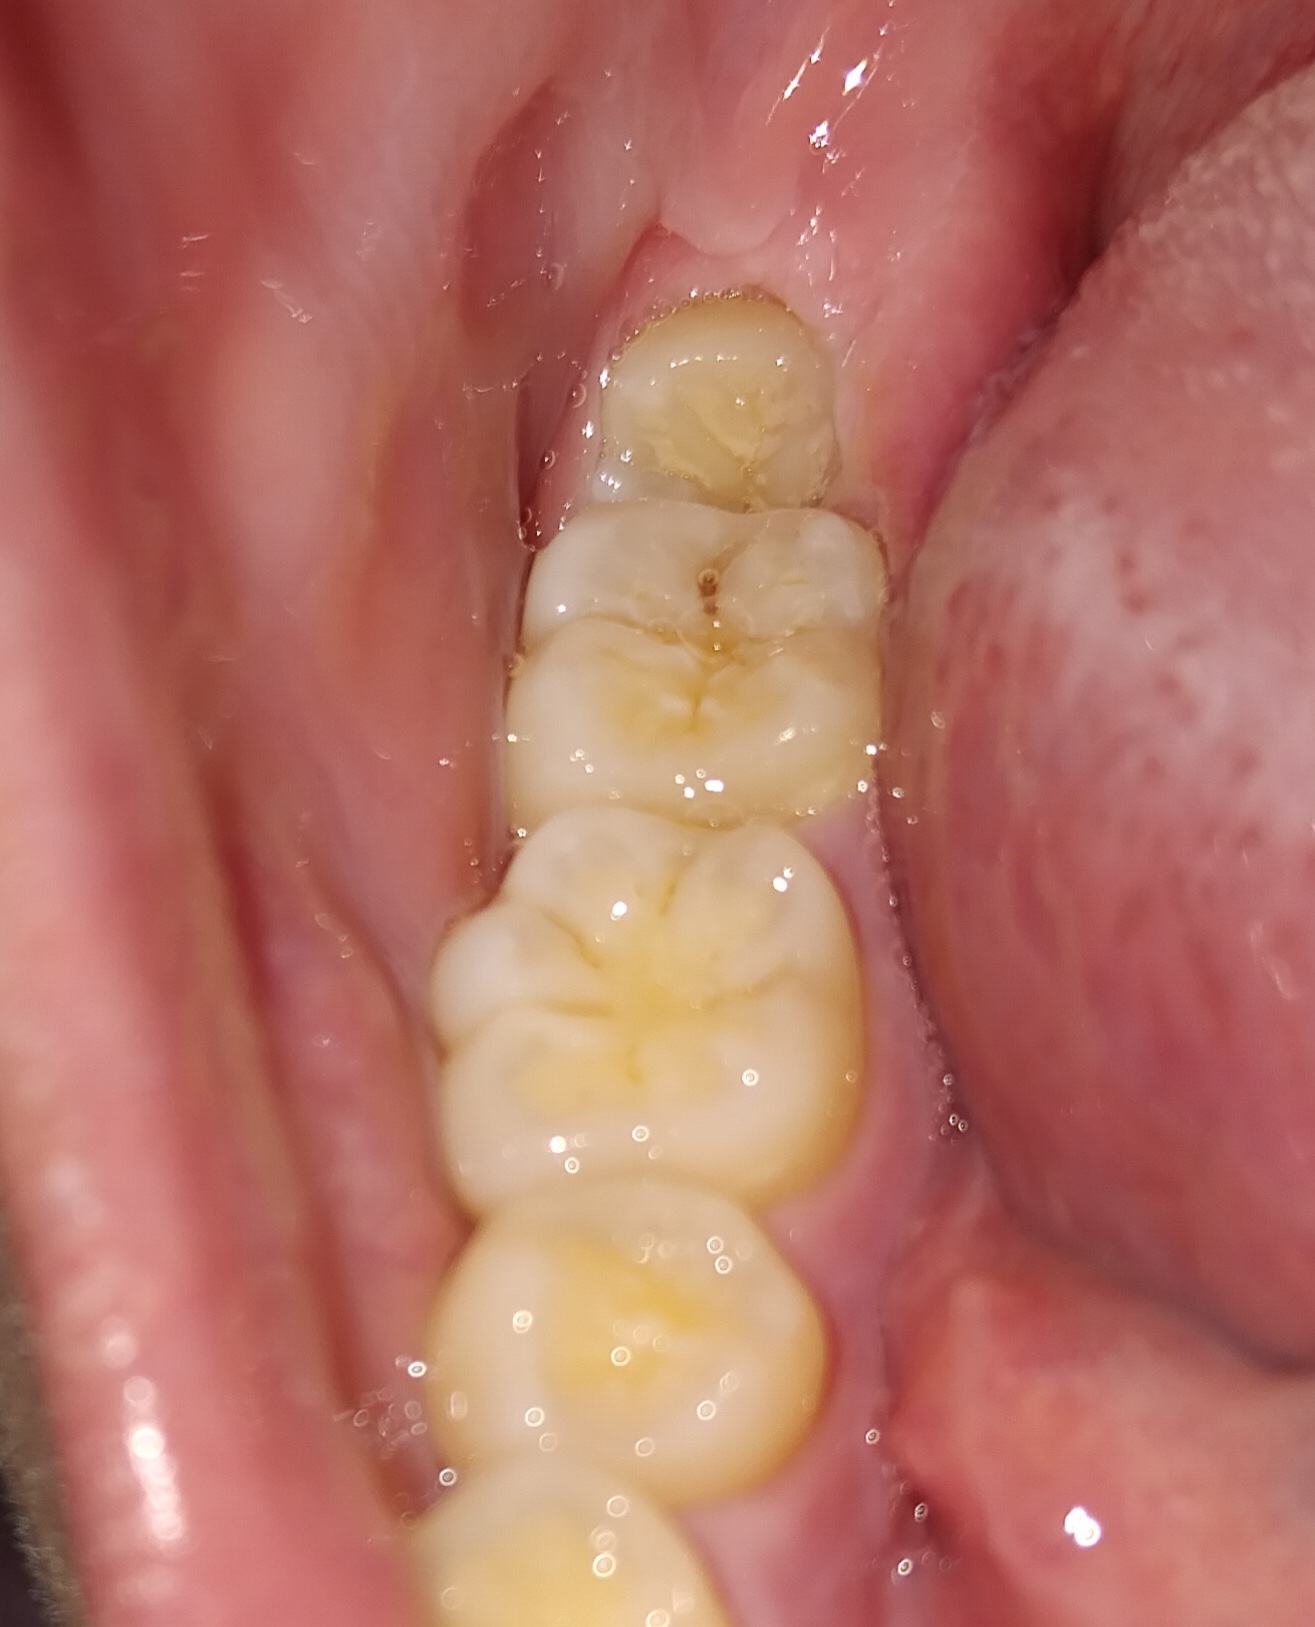

รู้สึกฟันกรามซี่ในสุดจะโยก ใช่เพราะฟันคุดไหมคะ

รู้สึกแปลกๆที่ฟันกรามซี่สุดท้ายพอลองโยกรู้สึกว่าฟันกรามซี่ในสุดจะโยกค่ะ ใช่เพราะฟันคุดไหมคะ ตอนแรกเหงือกบวมอักเสบพึ่งจะดีขึ้น ถ้าผ่าฟันคุดจะกลับมาแน่นเหมือนเดิมไหมคะ นัดผ่ากุมภา69ค่ะ ระหว่างนี้ทำอย่างไรได้บ้างคะ ระหว่างรอผ่ากลัวมันโยกหนักขึ้นค่ะ